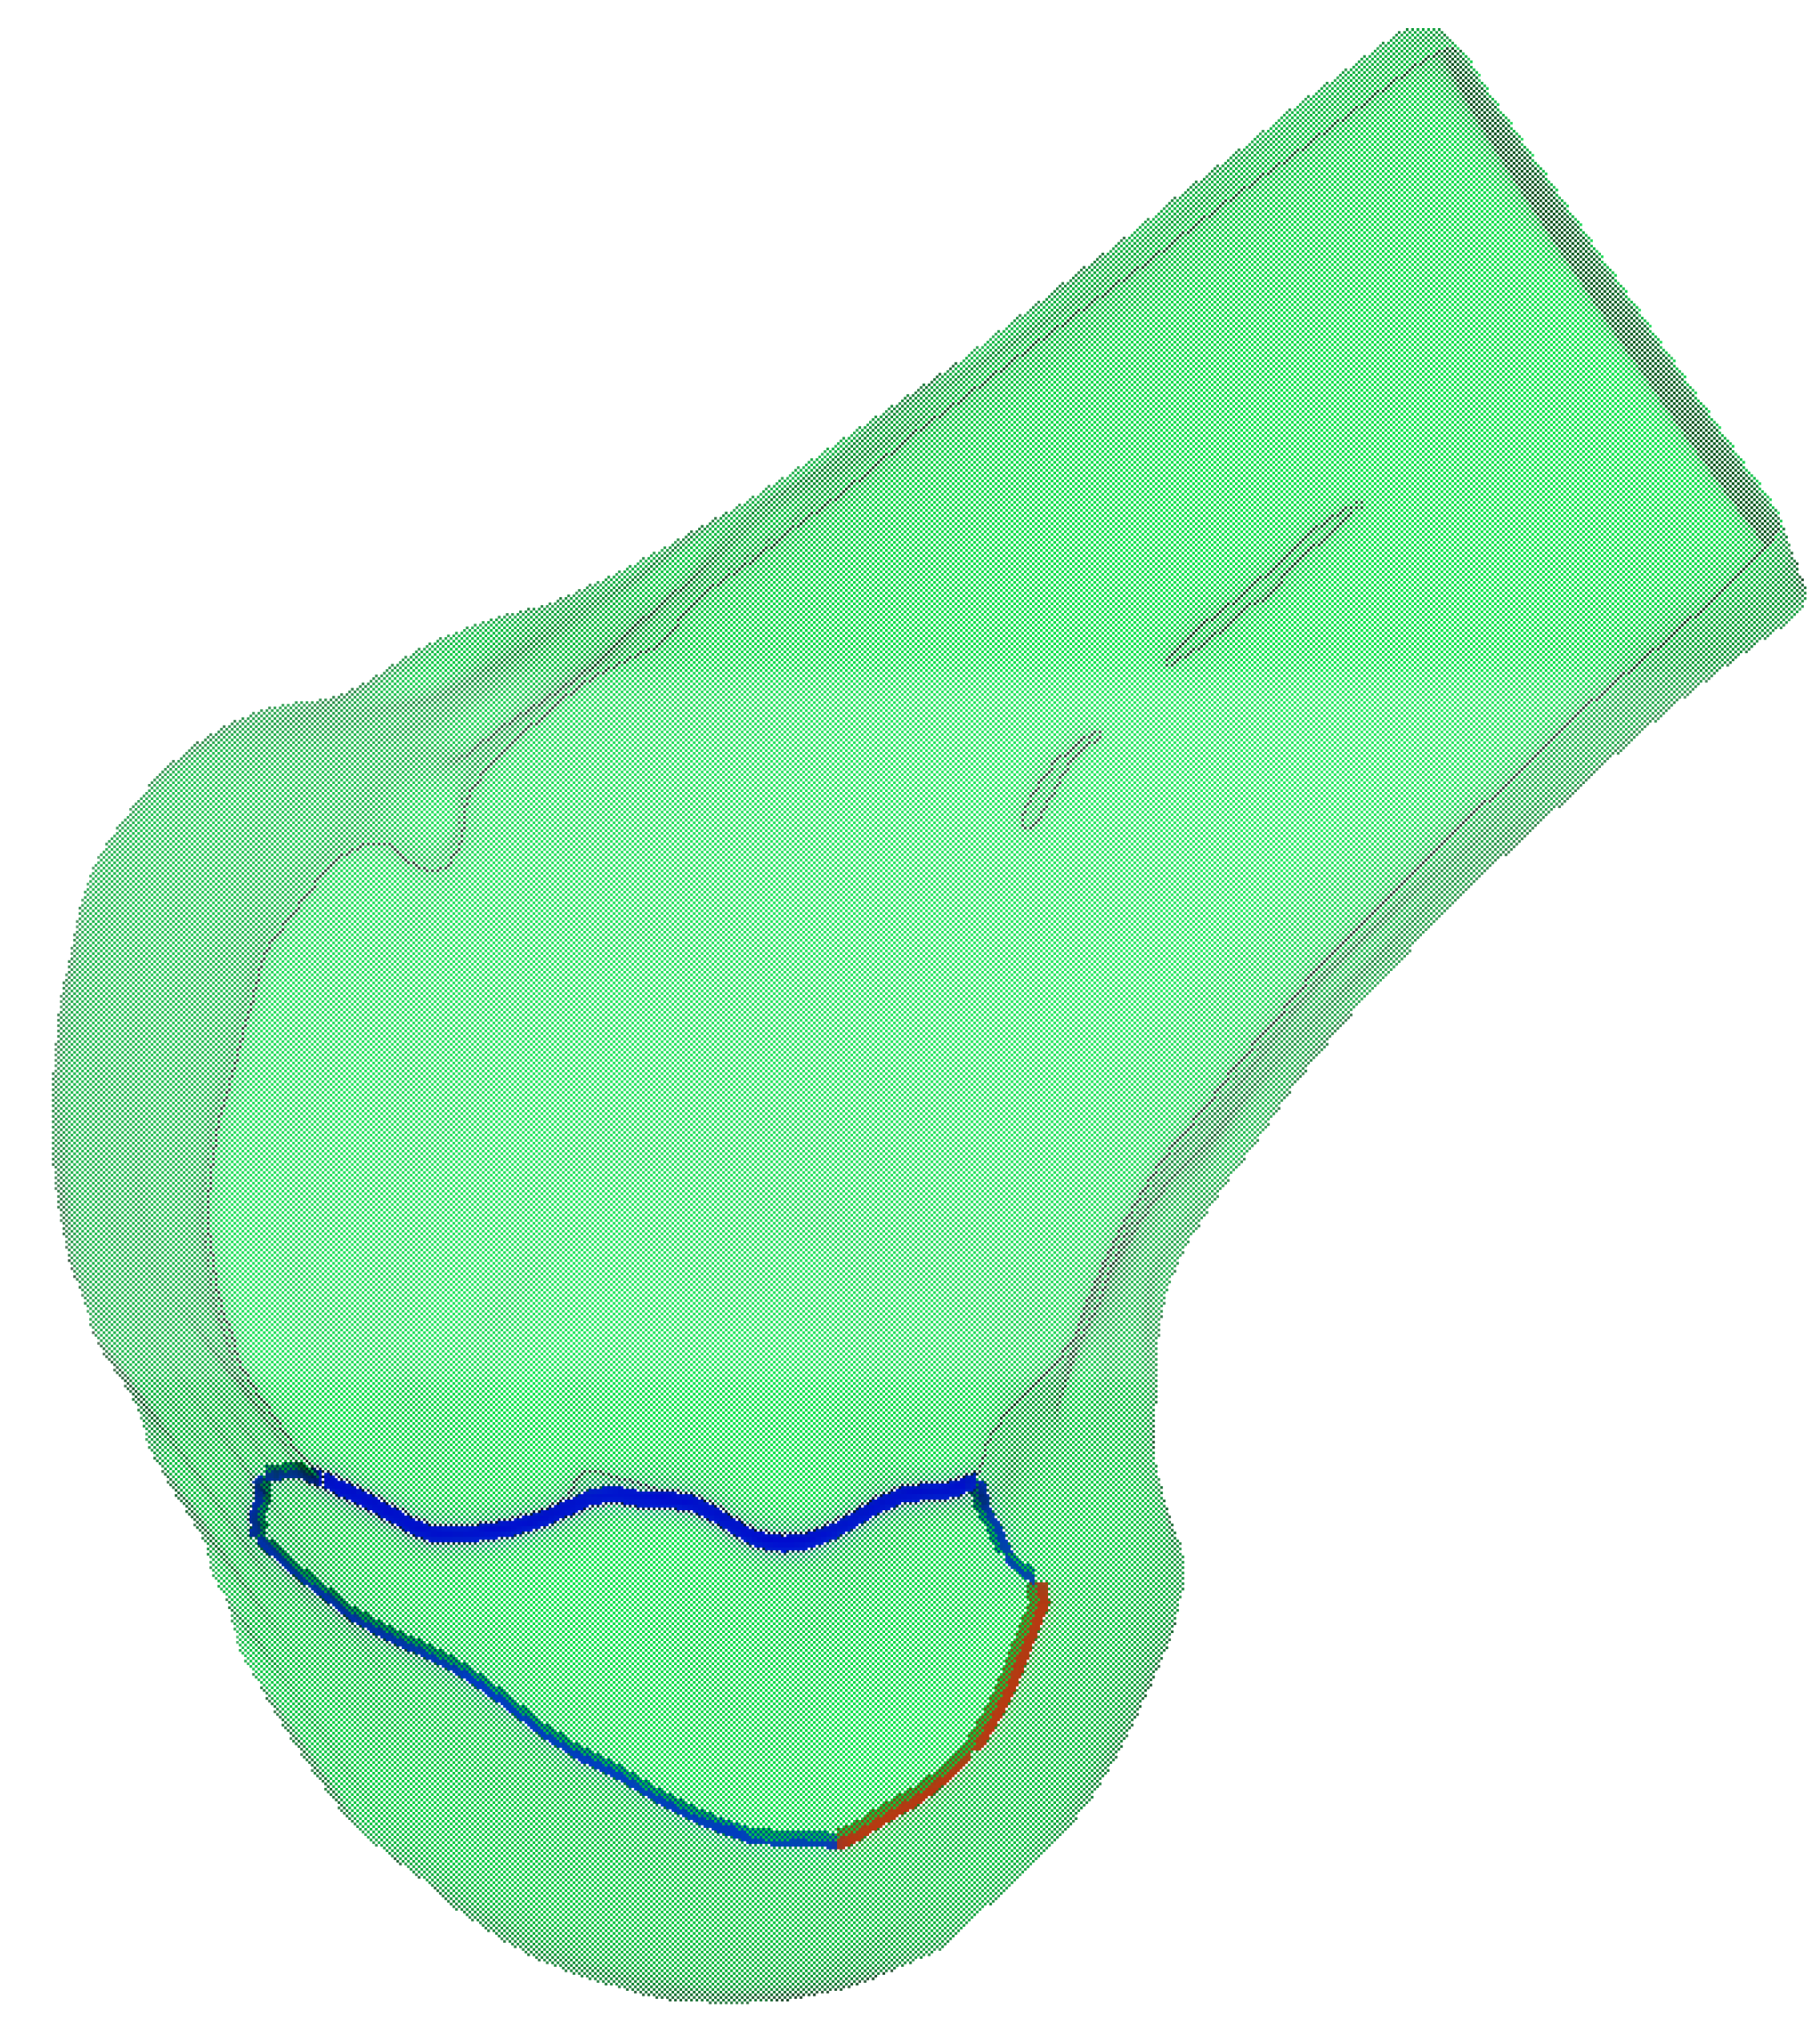

For the obtained 3D model of the lateral condyle, curvature analysis is first performed to identify key feature points. Given a 3D mesh model M = V , E , F , we employ discrete differential geometry methods to calculate local curvature characteristics for each vertex v i V on the mesh. The process begins with constructing a local coordinate system for vertex v i and considering its one-ring neighborhood N v i . By computing the mixed covariant derivative matrix and solving the eigenvalue problem, we obtain the principal curvature values κ 1 and κ 2 , which are then used to calculate the Gaussian curvature K v i = κ 1 κ 2 . Based on these curvature values, feature points in high-curvature regions are identified using a threshold τ , defined as P f = v i V   K v i > τ } . For connecting these feature points into continuous curves, we implement a region growing algorithm that starts from a seed point p s with the highest curvature value in P f . The algorithm iteratively searches for neighboring points that simultaneously satisfy three criteria, spatial proximity ( | p i p j |   ε ), curvature consistency ( K p i K p j   σ k ), and directional continuity ( t i , t j θ m a x , where t i and t j denote the unit tangent vectors at adjacent points). When no more qualified points can be found, a new seed point is selected from the remaining feature points. As illustrated in Figure 9, the complete workflow consists of Gaussian curvature computation, feature point identification, and curve generation through the constrained region growing process.

Based on the anatomically defined lateral condylar region Ω L , we perform spatial filtering on the previously extracted feature curves to obtain the clinically relevant portions. The feature curves are trimmed by intersecting them with the boundary of Ω L , resulting in two distinct curve segments, as shown in Figure 10. The red segment represents the clinically significant CLR, while the blue segment corresponds to the anterior articular margin. This anatomically constrained filtering ensures that the extracted geometric features accurately reflect the clinically relevant anatomical structures of the lateral femoral condyle.

Figure 9. Feature curve extraction on 3D mesh based on principal curvature analysis: (a) results of curvature computation; (b) feature point identification in high-curvature regions; and (c) connection of feature points into continuous curves.

Figure 10. Anatomically constrained feature curve extraction on the lateral femoral condyle. The blue curve represents the curvature-based feature curve extraction, while the red curve illustrates the anatomical region-based feature curve refinement applied to the blue curve.